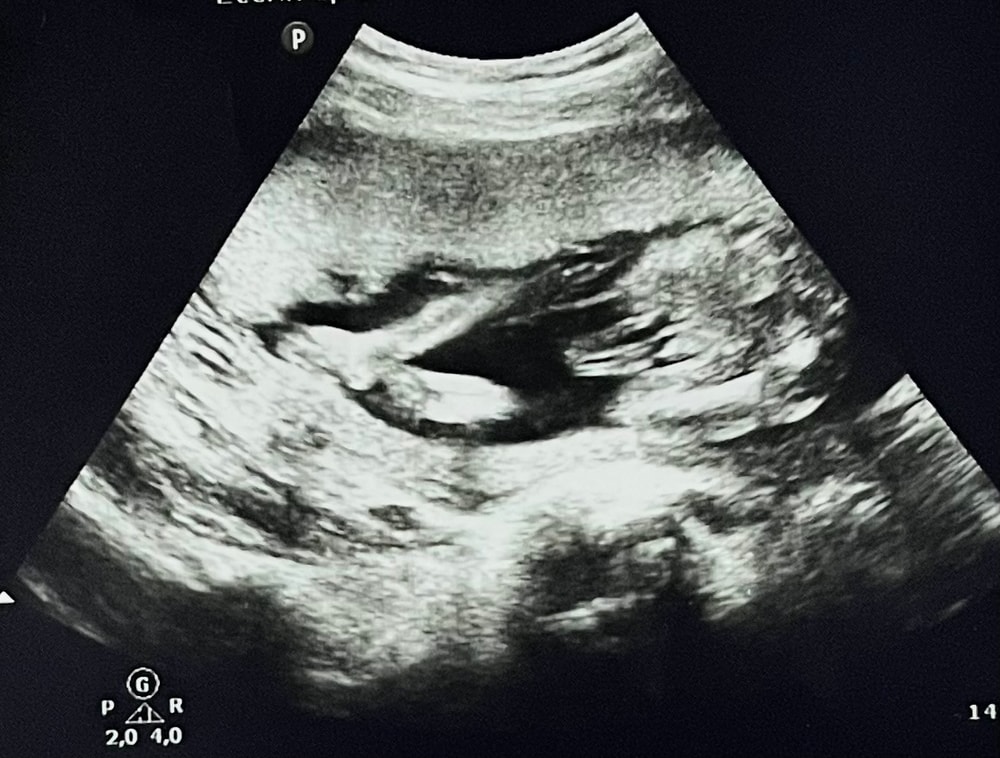

всем здравствуйте! недавно была на втором скрининге. На первом сказали, что у меня мальчик, а на втором - девочка. По фото узи у меня появились сомнения, потому что половой орган выпирает и не похож на девочку. Помогите определить)

Между ножек вроде похоже на кофейное зёрнышко, я бы предположила девочку

Снимок не очень четкий, но вроде бы девочка. Выпирает не орган, а фрагмент пуповины.

Фото размазанное ,не особо понятно,но у девочек на узи тоже половые губы "выпирают"